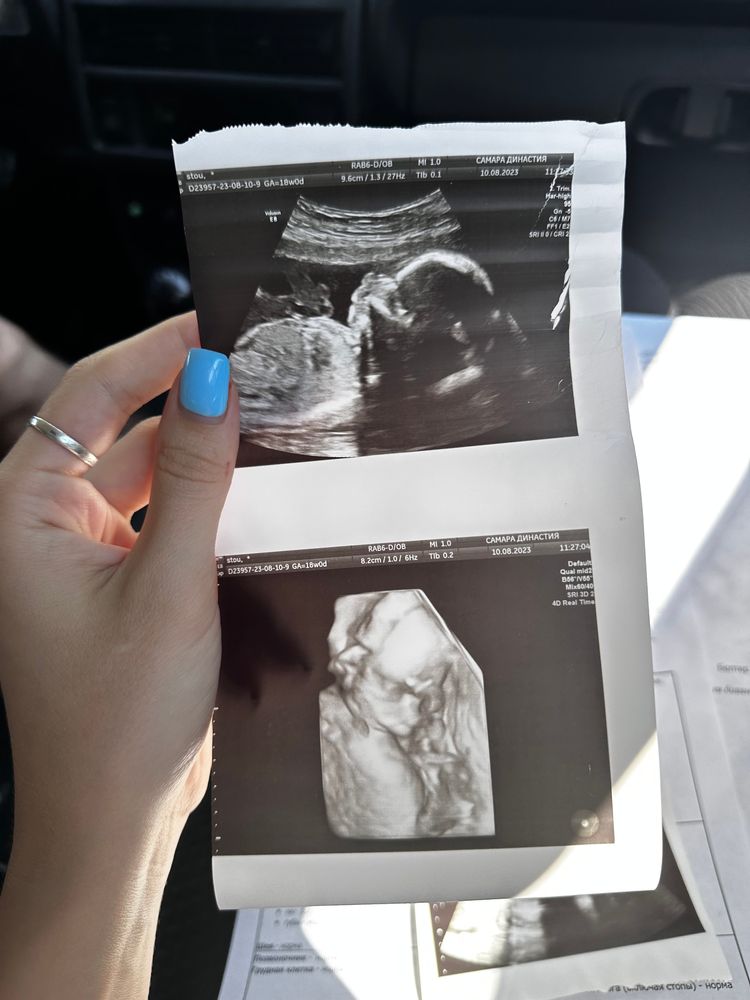

Вот и второй скрининг пройден!🥰 19 и 4 недели

У нас все хорошо!

Малыш лежал правильно, смотрела меня узист от силы минут 10-15, говорила как хорошо все видно, какой красивый малыш☺️ ручки и ножки длинные(есть в кого😄)

Пол я просила не говорить, она написала его на фотографии и запечатала, узнаем только 27 августа, но подкрадывается мысля что это мальчик, потому что пол она увидела ну оочень быстро)

По сроку мы так же опережаем, идем ровно по первому скринингу, и пдр так и стоит в Новый год 😅